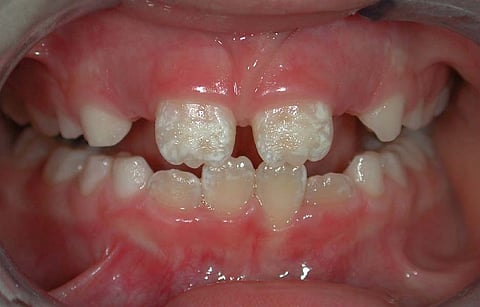

शोधकर्ताओं में शामिल विश्व-भारती, शांतिनिकेतन के शोधकर्ता अंशुमान चट्टोपाध्याय ने इंडिया साइंस वायर को बताया कि “हमने पाया कि अध्ययन क्षेत्र में शामिल गांव नोआपाड़ा में रहने वाले अधिकतम लोग स्वीकार्य सीमा से अधिक फ्लोराइड युक्त पानी पीने से फ्लोरोसिस से ग्रस्त हैं। वे कूल्हे, जोड़ों और रीढ़ की हड्डी में दर्द जैसी गंभीर समस्याओं से पीड़ित हैं, जो हड्डियों के फ्लोरोसिस के लक्षण हैं। इसके साथ ही, दांतों के फ्लोरोसिस के मामले भी देखे गए थे। लेकिन, हैरानी की बात यह है कि पीने के पानी में मौजूद फ्लोराइड की मात्रा और मूत्र नमूनों में पाए गए फ्लोराइड के स्तर के बीच संबंध स्थापित नहीं किया जा सका।”

शरीर में फ्लोराइड अथवा हाइड्रोफ्लोरिक अम्ल के अधिक प्रवेश होने से फ्लोरोसिस रोग होता है। फ्लोराइड मिट्टी अथवा पानी में पाया जाने वाला तत्व है जो आमतौर पर पीने के पानी अथवा भोजन के जरिये शरीर में प्रवेश करता है। इसके कारण दांत, हड्डियां और अन्य शारीरिक अंग प्रभावित हो सकते हैं।